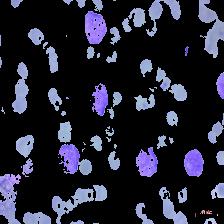

Figure 4: Sample images

Fig. 4 displays sample images, with (a) illustrating different malignancy stages, (b) demonstrating custom CIS application, (c) showcasing Gaussian blur, and (d) depicting histogram equalization.